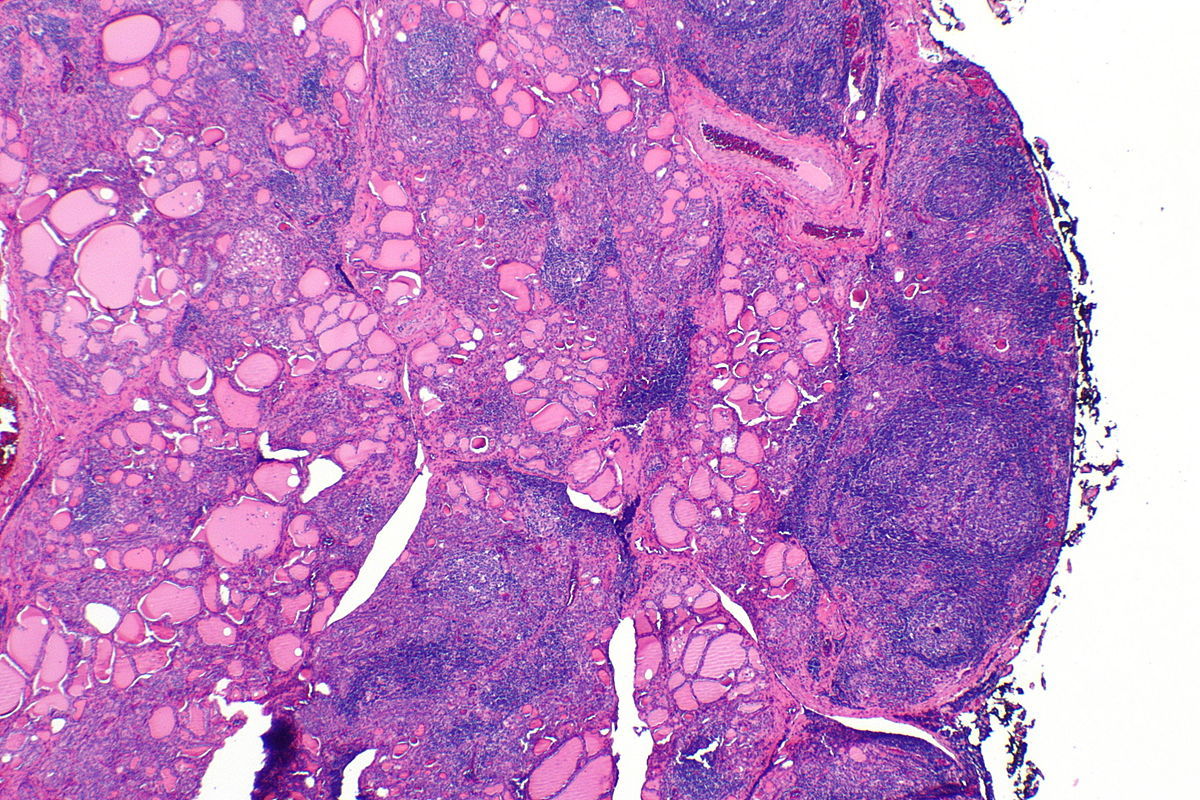

H&E of thyroid below shows pale staining area around the periphery of follicular space due to excess colloid use.

Thyroid Follicle

Colloid